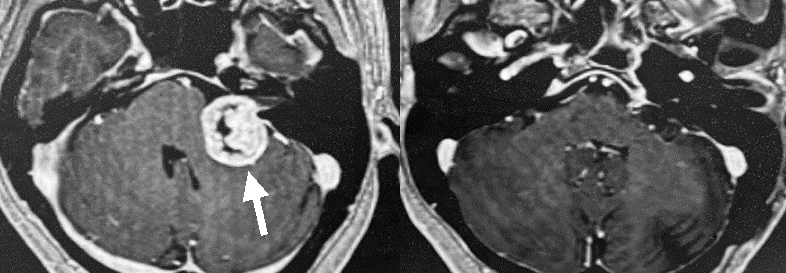

左の比較的大きな聴神経腫瘍です(一番左のMRI写真の黒矢印)。腫瘍内部が黒く、液体成分を多く含んでいることがわかります(嚢胞性といいます)。開頭手術により腫瘍は全摘出しました(左から2番目のMRI写真)。術直後から顔面神経機能は完全に正常でした。この手術では内耳道とよばれる部位の後壁をドリルで削る必要があります(右から2番目のCT写真の赤矢印の部分)。一番右のCT写真(手術後)では、その部分が削られていることがわかります(白矢印)。